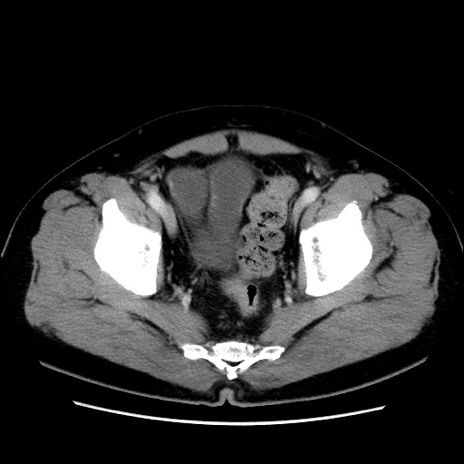

症例16(横断像)

【症例】 70歳代男性

【主訴】 腹痛、嘔吐

【現病歴】 約1ヶ月前より間欠的に腹痛と嘔吐あり、当院消化器内科を受診したところCTで多発する肝臓のLDAを指摘され、精査中であった。以降は消化器症状は安定していたが、2日前より嘔気と腹痛があり、同日より排便・排ガスが消失した。改善認めず、 本日、救急外来を受診した。

【既往歴】 大腸ポリープ切除後。

【身体所見】意識清明・会話良好、BT 36.3℃、BP 127/80mmHg、 P 80bpm、腹部:膨満あり、平坦・軟、上腹部正中および下腹部正中に圧痛あり、反跳痛なし、筋性防御なし。

【データ】WBC 7200、CRP 0.77